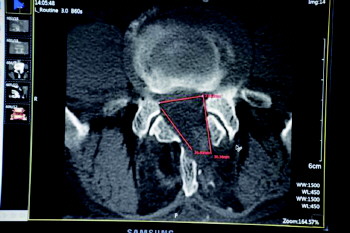

提起开刀手术,王先生就忐忑不安。想到四年前儿子“腰椎间盘突出”就是被林主任给治好的,就抱着极大的希望再次找到了林主任。接诊后,林主任立即为他做了专科查体,并进行了腰椎核磁和CT检查。检查发现,王先生的腰椎管巨大突出处于L4/5,正好压迫着腰部神经根组织,并且椎管内增生狭窄严重,这也是他病情发展迅速、疼痛加重的根源所在。